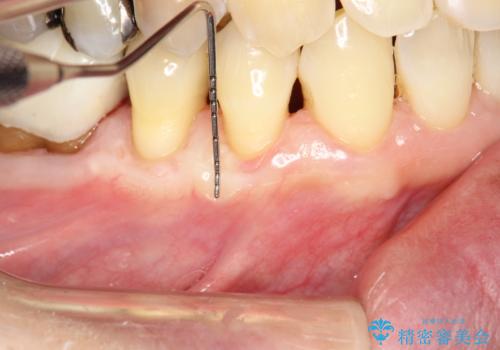

術後3ヶ月にて意図した通りに丈夫な歯肉の幅が増大し、厚みも十分に確保できました。

これで歯肉が下がることを気にせずしっかりとブラッシングしていただく事が可能になりました。